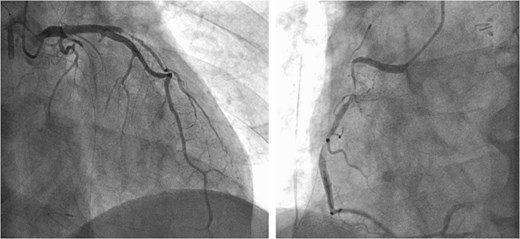

Following closure of the PA and cessation of cardiopulmonary bypass, ST-segment elevation was observed, accompanied by a deterioration in the patient's hemodynamics. Consequently, an intra-aortic balloon pump (IABP) was inserted via the right femoral artery and coronary angiography (CAG) revealed spasms along the entire length of the RCA and obtuse marginal artery (Fig. 5). These spasms improved generally after administration of nitroglycerin (Fig. 6). However, ventricular fibrillation was provoked, leading to unstable hemodynamics. Therefore, veno-arterial extracorporeal membrane oxygenation was initiated, and the surgery was concluded. Extracorporeal membrane oxygenation (ECMO) and IABP were withdrawn 4 days and 5 days after surgery, respectively. The patient's postoperative course was good, and he left the hospital on post-operative day 20.

Intraoperative CAG revealing vasospasms along the entire length of the RCA and OM artery.